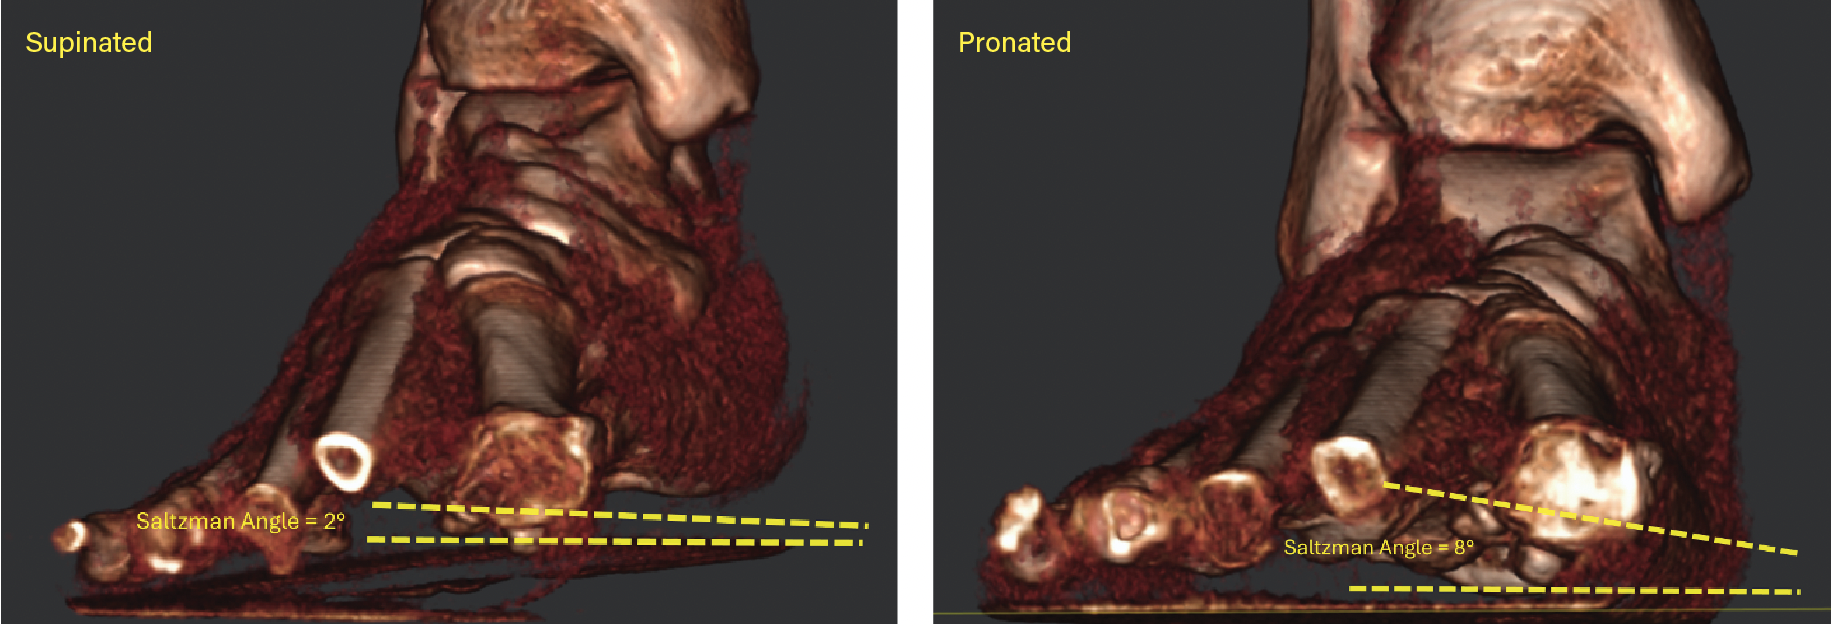

In terms of joint rotation, the first TMT joint moves in the direction of supination, not pronation in patient with HAV. Three studies using standard CT imaging compared joint positions of the medial column of the feet in both an unloaded and loaded condition. The studies compared these joint rotations in patients with HAV deformity and healthy control patients. Geng and colleagues observed that the first metatarsal moved in the direction of inversion, dorsiflexion and adduction relative to the medial cuneiform and the magnitude of this motion was greater in all 3 planes in the patients with HAV deformity.29 Watanabe found that both HAV patients and controls demonstrated equal magnitude of 5 degrees eversion of the navicular with loading of the foot, while the HAV patients demonstrated greater inversion (2 degrees) of the first metatarsal relative to the medial cuneiform than controls.45 There was minimal coronal plane rotation of the cuneiform in both groups. Kimura and colleagues found that the talonavicular joint rotated in the direction of eversion, with greater magnitude and variability in the HV group.46 At the first naviculocuneiform joint, the HAV patients showed eversion at a magnitude of only 0.2 degrees while control patients showed mild 1.5 degrees inversion. At the first TMT joint 4.9 degrees inversion occurred in the first metatarsal with loading of the foot. In addition, dorsal hypermobility of the first ray was present in patients with HAV deformity who exhibited more dorsiflexion at the first TMT joint than healthy controls. The overall net frontal plane motion of the medial column was in the direction of eversion, primarily due to motion of the navicular on the talus. Pronation motion of the navicular measured 9.6 degrees, which offset 4.9 degrees of supination motion of the first metatarsal at the first TMT joint. Therefore, when the entire foot pronates, the net pronation or eversion of the joints proximal to the first TMT articulation can ultimately place the first metatarsal everted to the ground (Figures 2A-E).

It is clear that the center of pronation rotation of the medial column of the foot in HAV patients is the talonavicular joint, not the first TMT joint. In the 3 studies of joint motion in HAV patients, the first TMT always moved in the direction of supination with loading of the foot.29,45,46